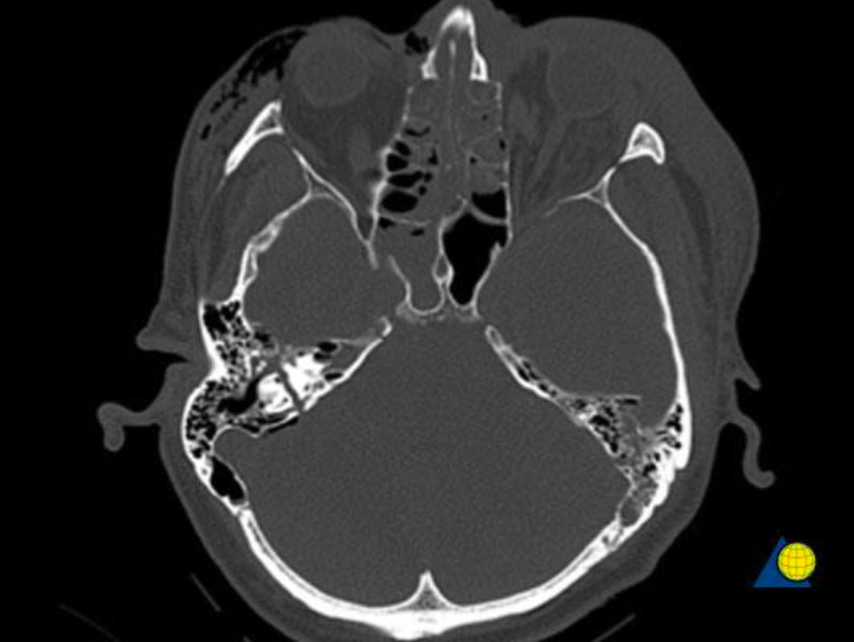

蛛網膜下腔出血 (SAH)

image